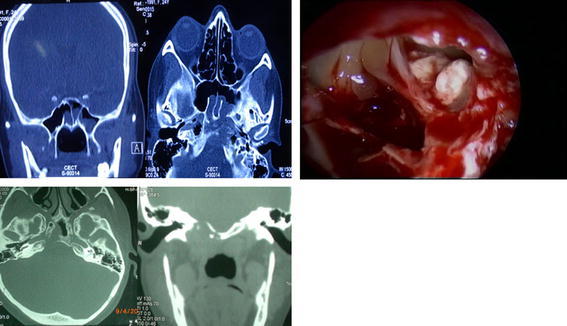

Fig. 1.

(Patient 1 and 2) NCCT revealed heterogenous mass in sphenoid sinus with erosion of posterior wall and roof and extension in right petrous apex region. The intraoperative photograph of patient 1 revealing white colour cheesy mass in sphenoid sinus